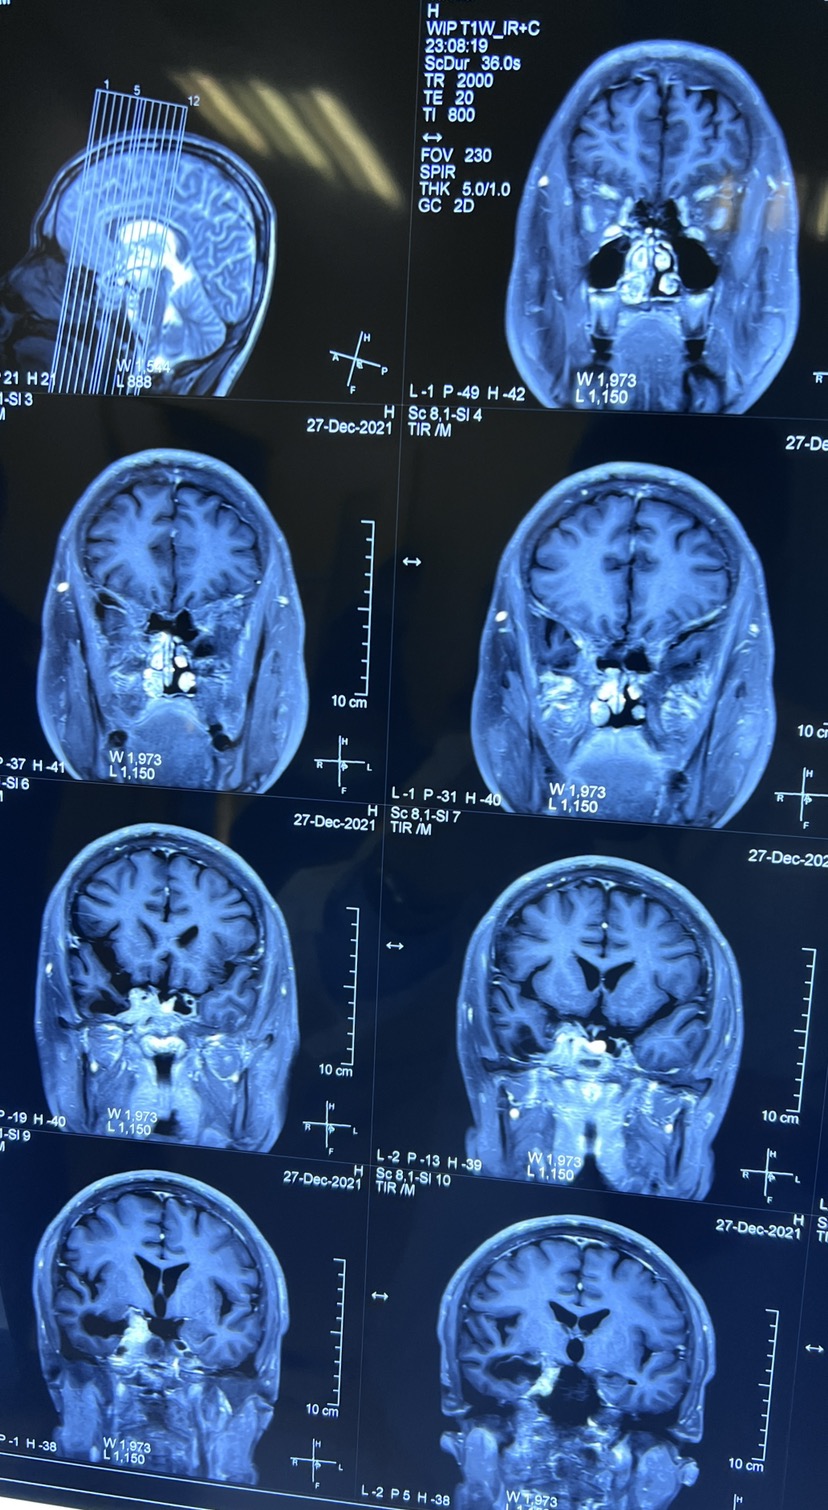

口服溴隐亭药物治疗3个月后

药物治疗后3个月复查核磁共振,发现肿瘤奇迹般的缩小,病人的一般状况也非常好。

药物治疗泌乳素型垂体瘤,即溴隐亭用药一定要规范,用药之后肿瘤可以明显缩小。提示这样的病例药物治疗优于手术。